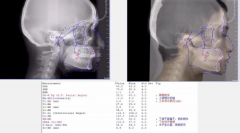

谢晓聪医生隐形矫治不对称拔牙案例分享

时代天使隐形正畸认证专家、暨南大学穗华口腔医院荔湾院区资深正畸医师谢晓...【详细】